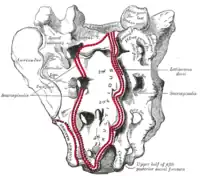

Corte sagital del sacro. Distribución posterior de los nervios pelvicos.

Distribución posterior de los nervios pelvicos.- Cara pélvica del sacro.

- Cara dorsal del sacro.

El borde anterior de S1 es sobresaliente y se denomina promontorio sacro. El vértice se articula con el cóccix. El orificio vertebral del sacro se denomina conducto sacro. Contiene las raíces nerviosas de la cola de caballo (raíces de nervios espinales situados debajo de L1). En las caras pélvicas y dorsal del sacro aparecen cuatro pares de orificios sacros a través de los cuales emergen ramos dorsales y ventrales de los nervios espinales.